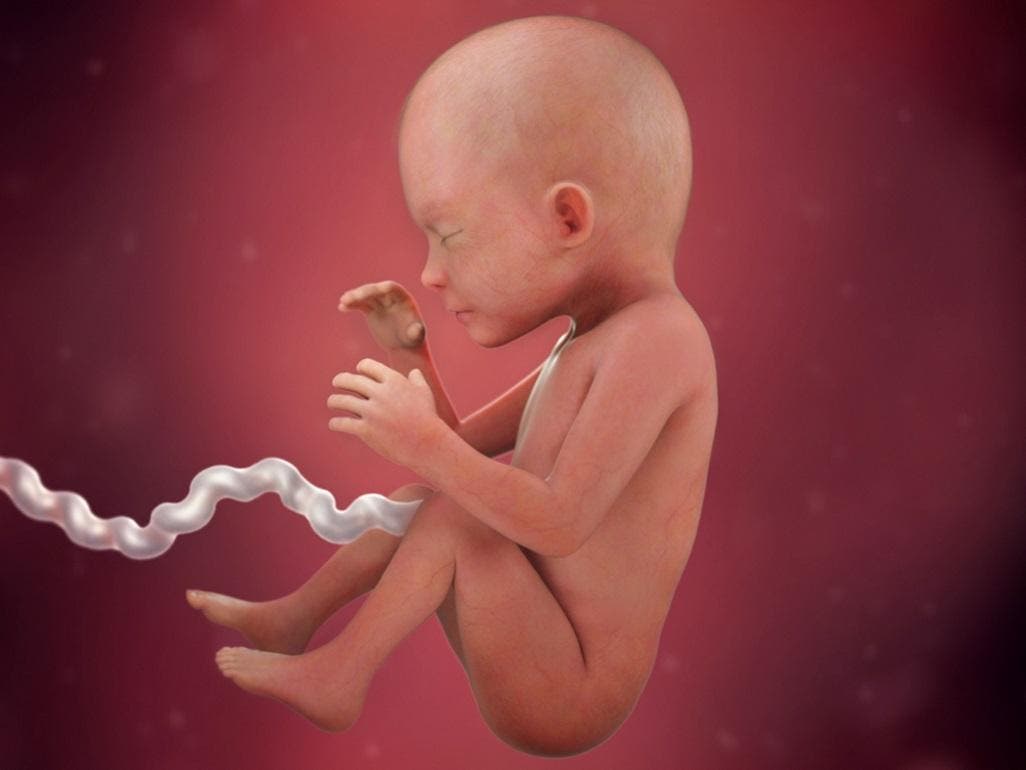

Yani hem siz çok heyecanlısınız hem de bebeğiniz çok hareketli… i̇şte gebelikte 30 hafta bebek gelişimi… bebeğinizin uyuma ve uyanma döngüsü artık düzene girdi. Hamilelikte hafta hafta bebek gelişimi konusunda sitemizde yer alan videoları izlemek size de iyi gelecek ve sürece psikolojik olarak hazırlanmanızı sağlayacaktır. Bebek doğmaya hazır hale gelene kadar hem annede, hem de bebeğin kendisinde pek çok değişim meydana geliyor. Fetüsün başı hala karnına doğru. Bütün bu etmenler fetal kiloyu tahmin etmeyi zorlaştırır. 7 haftalık gebelikte bebek gelişimi sabittir. Hamilelik dönemi boyunca bebeğin anne karnında geçirdiği sürenin oldukça önemli olduğunu belirten uzmanlar, bebeğin sağlıklı gelişimi için anne karnında geçirdiği. 7 haftalık hamilelikte bebeğin parmakları hala birleşiktir. Boyu ne kadardır, gibi bilgileri aşağıdaki tablomuzdan görebilirsin.

39 haftalık gebelikte bebek gelişimi tamamlanır ve doğuma hazırdır. Bebeğiniz premature (erkendoğan) ise gelişim evreleri diğer bebeklere göre daha yavaş olacaktır. Uykuda oldukları zaman sırtüstü yatmalıdırlar ancak boyun kaslarının gelişimi için uyanıkken karın üstünde vakit geçirmelidirler ki ilerleyen zamanlarda kendini ileri itme, oturma ve emekleme yaparken bu kaslara çok ihtiyacı olacaktır. 9 haftalık gebelikte bebek boyu ortalama 2 cm, ağırlığı ise yaklaşık 2 gram kadardır. Gelişimsel rehber sadece geçireceği evreleri belirtir, bebeğinizin gelişimi hafta hafta buna uymayabilir ancak er yada geç bu süreci takip eder. Haftada bebeğin kas kütlesinin gelişmesiyle birlikte hareketlerin şiddeti de artar ve daha kolay.

Bu haftada plasenta bebekten çok daha büyüktür. Haftalık bebek gelişimi, ay ay bebek gelişimi, persentil olarak bebeğinizin gelişim tablosunda nerede yer aldığı ve gelişim evrelerine göre ne kadar hızlı veya yavaş olduğunuz akla gelir. Buna inanmayacaksın ama bebeğinin kilosu, şu andan itibaren doğuma kadar tam 15 kat artacak. Ve 9 haftalık bebek embriyonik dönemden fetal döneme geçiş yapmaktadır. Bebeğin amniyon kesesinin içinde büyüyor olması, onu dış etkenlere karşı korumaya alır. Şimdiye kadar embriyo olarak gelişimini sürdüren bebeğinizin fetüs olmasına sadece 1 hafta kaldı.

7 haftalık bebek anne karnında c şeklindedir, baş ve kuyruk kısmı belirgindir. Uykuda oldukları zaman sırtüstü yatmalıdırlar ancak boyun kaslarının gelişimi için uyanıkken karın üstünde vakit geçirmelidirler ki ilerleyen zamanlarda kendini ileri itme, oturma ve emekleme yaparken bu kaslara çok ihtiyacı olacaktır. 7 haftalık gebelikte bebek gelişimi.

9 haftalık bebeğin gelişimi organlarda, kol ve bacaklarda belli olmaya başlar.b u haftada bebeğin artık neredeyse tüm organları, kafası, gövdesi, kolları ve bacakları belirmeye başlamıştır. Bunun nedeni, bu aşamada vücudunuzdaki kan miktarının artması ve mesanenizde ekstra basınca neden olan çok fazla sıvı olmasıdır. 7 haftalık hamilelikte bebeğin parmakları hala birleşiktir.

5 ay ve 2 haftalık hamileliğe karşılık gelen 22 haftalık gebelikte bebek gelişimi, annelerin bebeklerinin daha sık hareket ettiğini hissetmeleriyle karakterizedir. Haftalık bebek gelişimi, ay ay bebek gelişimi, persentil olarak bebeğinizin gelişim tablosunda nerede yer aldığı ve gelişim evrelerine göre ne kadar hızlı veya yavaş olduğunuz akla gelir. 9 haftalık gebelikte bebek boyu ortalama 2 cm, ağırlığı ise yaklaşık 2 gram kadardır.